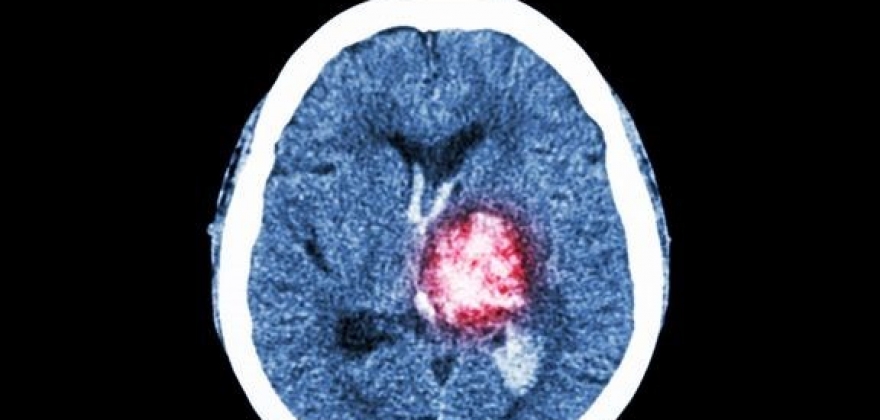

Flere vil kunne overleve hjerneblødning

Hjerneblødning tar livet av like mange i dag som på 1990-tallet. Det trenger ikke være slik. Med bedre behandling kan de som får hjerneblødning leve lenger.